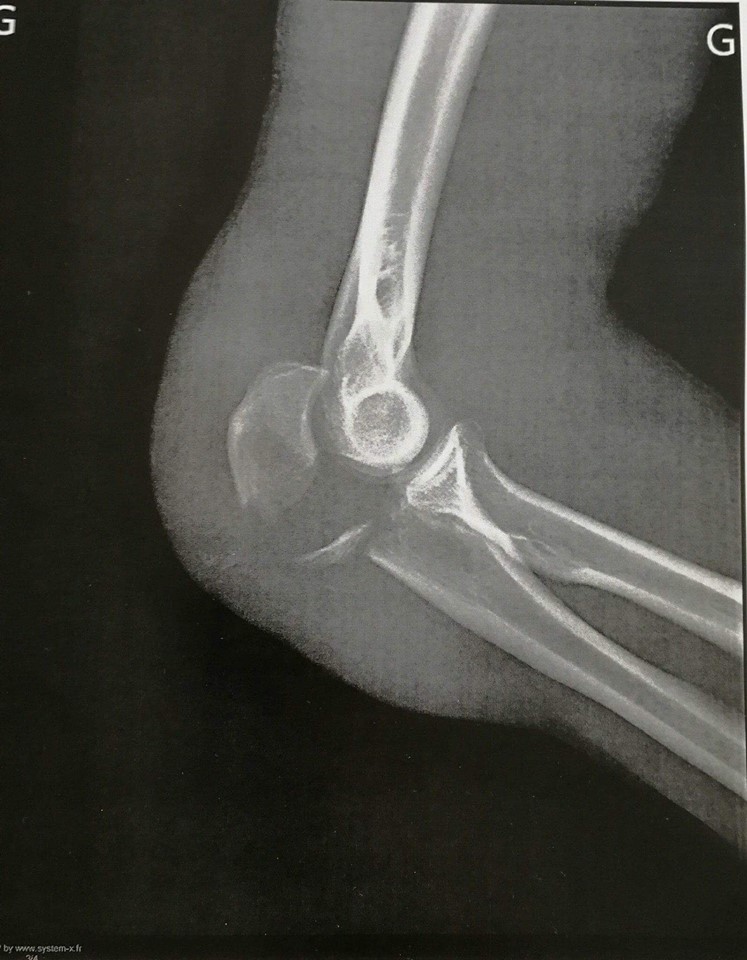

« Tout s’est passé super vite ! Avec la vitesse, je n’ai pas eu le temps de bien tomber. Il semblerait que j’ai posé la main en premier, mais sûrement un peu de travers et avec la vitesse ça m’a complètement explosé le coude. Quand je me suis relevé j’avais le coude déboîté et plus de sensibilité dans le bras donc je l’ai remboîté… Puis en touchant l’arrière du coude, j’ai senti qu’il n’y avait plus un os mais quelques morceaux qui se baladaient, pas top quoi ! »

« Il est venu me ramasser, puis m’a de suite emmené à l’IM2S (Institut Monégasque de Médecine du Sport). La prise en charge était vraiment top j’ai été opéré moins de 5h après ma chute. Ils m’ont mis des broches et un fil de fer apparemment, pour attacher tous les morceaux ! Haha !! »